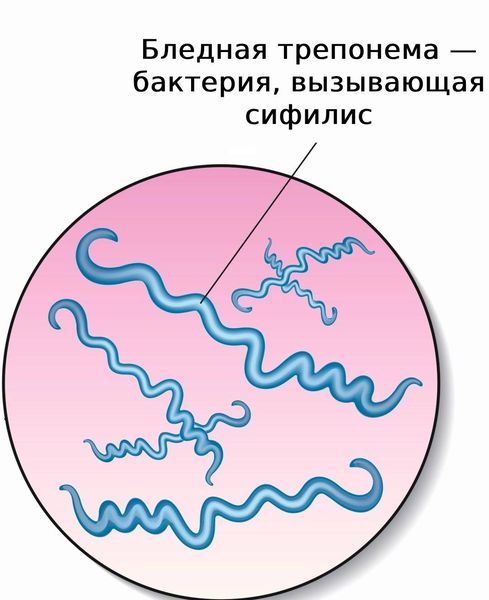

Врождённый сифилис начинается со взаимодействия Treponema pallidum с плодом. Предполагают, что основную роль в механизме возникновения заболевания играет иммунный ответ плода на бледную трепонему с образованием противосифилитических антител.

Заражение плода происходит трансплацентарно, начиная с 16–18 недель беременности, через пупочную вену. Treponema pallidum попадает в системный кровоток плода, вызывая генерализованную инфекцию с поражением костей, печени, селезёнки, почек и центральной нервной системы. Поэтому лечение матери необходимо начинать до этого срока, чтобы избежать инфицирование плода [9].

Treponema pallidum